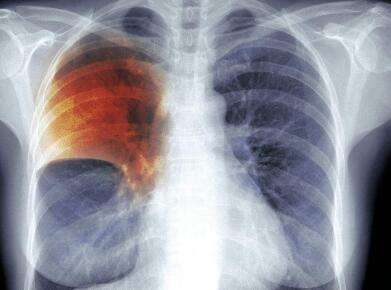

学生患肺结核

桃江县疾控中间称 该校发明有30余例肺结核疑似病例 校方称学生之前未解释病情直到8月才懂得

近日,有网友向北京青年报记者反竽暌钩,湖南省益阳市桃江虾?中群发肺结核,该校学生表示已稀有十人患病。昨日,本地县委宣传部在官网宣布传递称,截至11月15日,近90%的患病学生已经复学或者可以复学。桃江虾?中校长在接收北青报记者查访时称,此前有学生隐瞒病情,本身直到8月份才懂得情况。

陈丽华(化名)无论若何也想不到,本身竟然会因为患上肺结核在备战高考的关键时刻休学。本年8月,陈丽华地点的桃江虾?中高三年级文科优生班364班有几十人被确诊患上肺结核。陈丽华说,“班主任叫了三个同窗谈话,这时刻我们才知道班里有人患上了肺结核”。

8月10日,桃江虾?中组织364班同窗做了一次血液检查,查出7人患有肺结核。随后在家长的请求下,8月19日开端陆续有家长带自家孩子前去病院检查。张清艺(化名)也是364班学生,据她介绍,第一批学生确诊之后,黉舍采取了消毒等办法,确诊有感染性的同窗都休学在家。一位确诊学生家长告诉北青报记者,8月份之后,又有不少家长带孩子做了检查,陆续发清楚明了一些结核病患。11月13日,桃江四中再次组织一向在校上课的364班同窗检查,又发清楚明了14例确诊病例。

针对此次肺结核集中爆发的情况,北青报记者以学生家长的身份咨询了桃江县疾控中间。一位工作人员称,8月份到9月份时代,他们对四中全校所有学生进行了一次筛查,总共发明30多例疑似病例,个中20多例最终被确诊。

桃江县疾控中间结核科一名工作人员表示,结核病的埋伏期比较长,感染后随时可能发病,所以存在隔一段时光出现个别新增病例的情况。他们没发病时和正常人一样,只有发病后才能查出来。

原标题:湖南一中学群发肺结核 确诊20余例